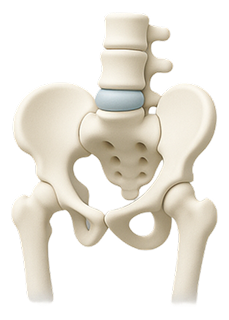

When the soft center of a spinal disc pushes through a crack in the exterior, it can press on nerves and cause pain.

Common Causes of Lower Back Pain

Lower back pain can stem from several underlying issues, including: